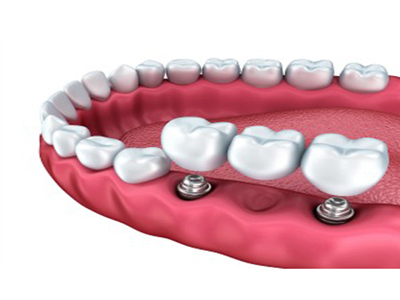

Case : Single implant placement in missing teeth site